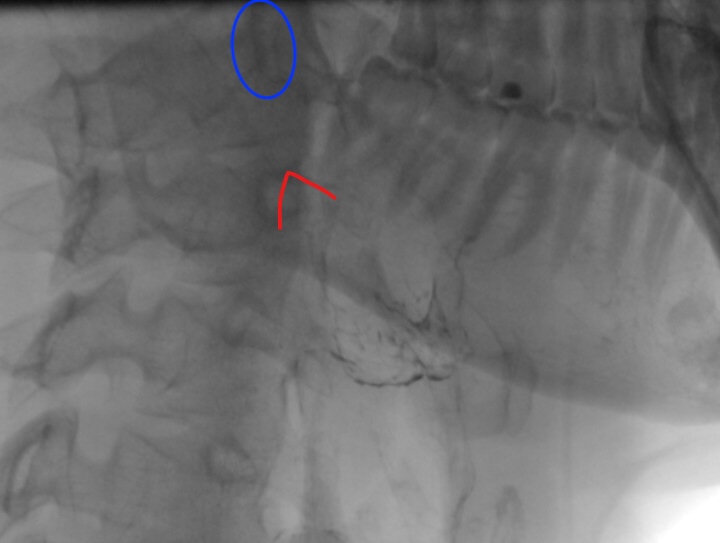

I’ve circled what looks like it could be the tip of your styloid in your image, but it’s not the whole thing. A CT scan w/ & w/o contrast between skull base & hyoid bone is the best way to see what’s going on in your neck. If you can get the scan done dynamically (w/ your head turned L/R & looking up/down) that can show things that a neutral head position doesn’t show.

I’ve also included a front-on image and highlighted around the bit that I think shows the styloid process. Is that it, or something else?

@carl - OOPS! Sorry about that! I added the image I annotated to my previous post. I can faintly see the styloid you outlined. Getting a CT scan w/ contrast as previously mentioned will be the best way to see how your styloid may be playing into your symptoms, especially the vascular ones.